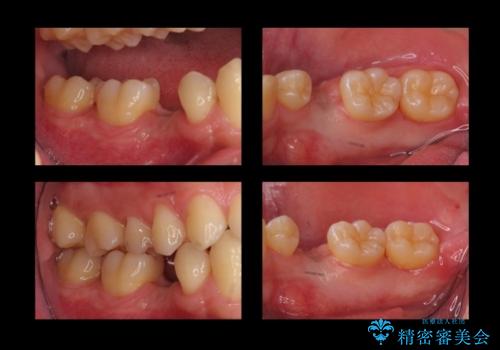

- 当院で矯正治療後、奥歯(前から5番目の歯)のインプラントを行いました。

元々乳歯が残っており、永久歯が欠損していました。

また、一番後ろの永久歯(7番目)の周りに骨がたくさんあり、そこの骨の形を整えて削ってあげたほうが、7番目の歯がしっかり歯茎の炎症も治りやすい状況でした。

そのため、5番目のインプラントと、7番目の骨整形を同時に行い、整形で取れた7番目の骨をインプラント周囲に移植し、骨を増やすことにしました。

矯正治療の経過は以下に示しています。